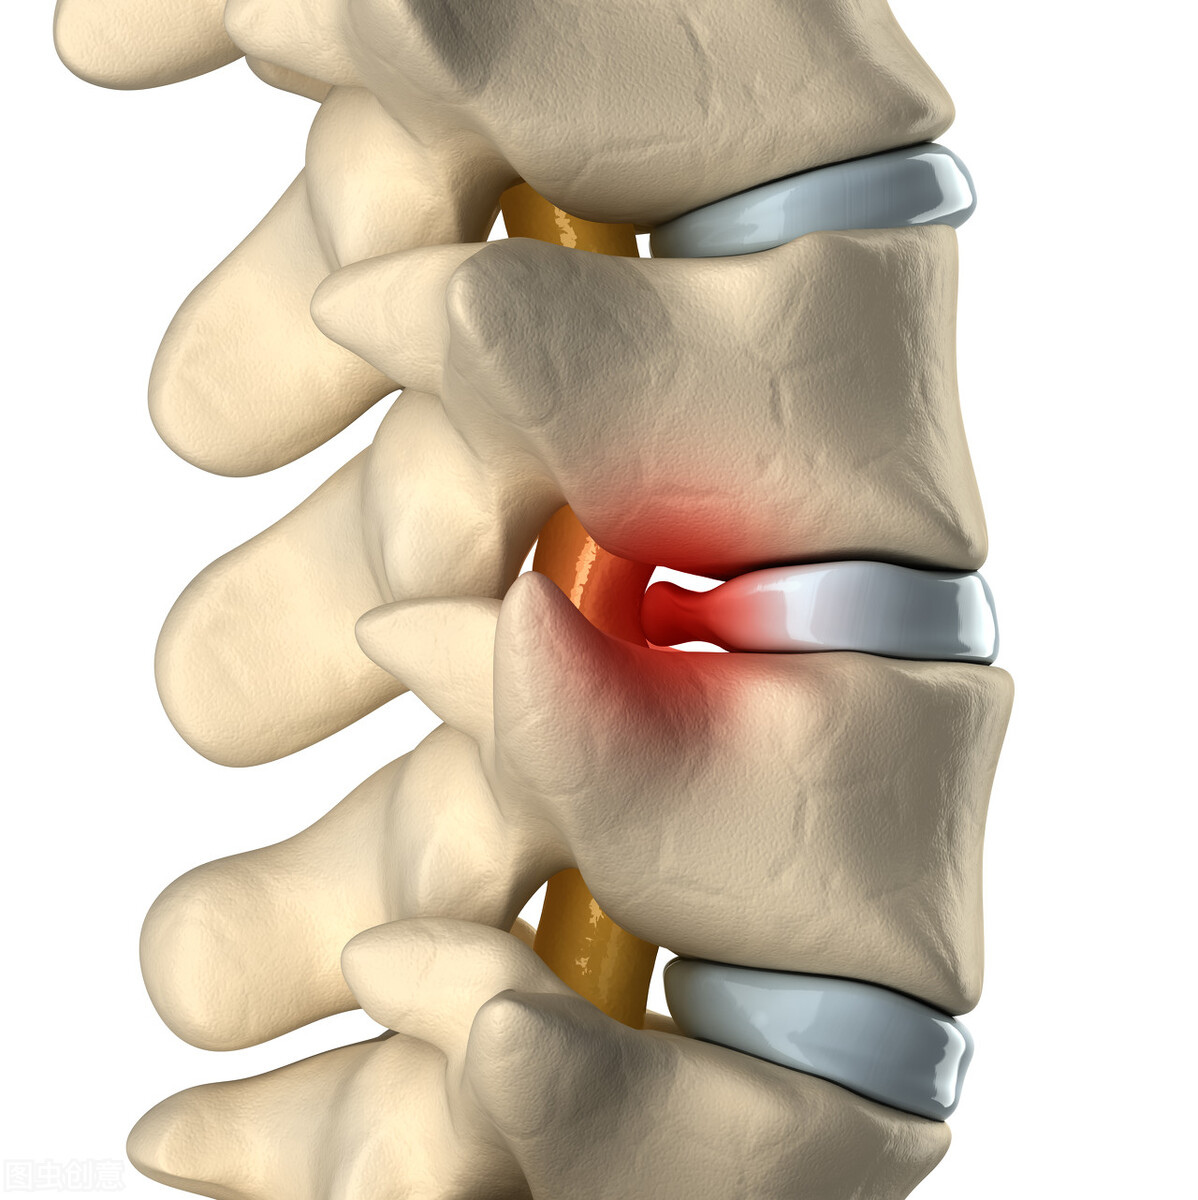

腰椎间盘突出 是由于腰椎间盘退变、劳损、损伤而使纤维环破裂,导致髓核组织突向后面的椎管,压迫、刺激神经根造成的一系列的症状。

- 椎间盘突出压迫硬脊膜主要表现为腰痛,压迫神经根则表现为坐骨神经痛。

- 椎间盘突出不明显而纤维环有破裂,其内的髓核被挤出,化学性炎症刺激神经根而出现典型的坐骨神经痛。